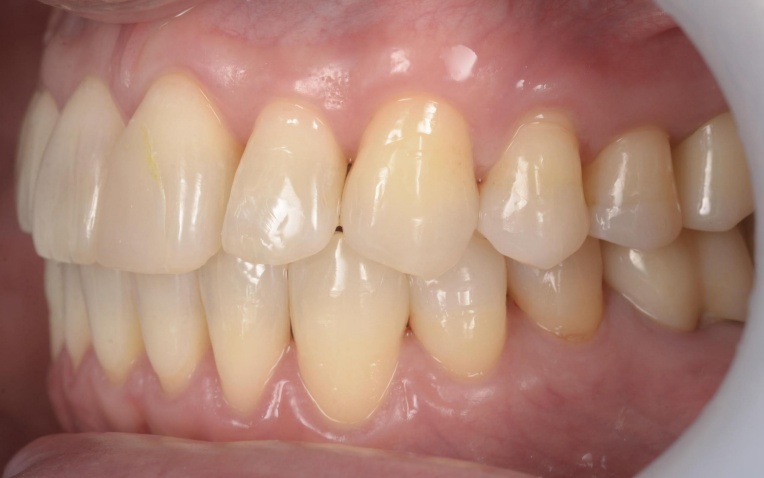

治療前

治療後

拝見したところ、右下奥歯(第2大臼歯)が折れていることが確認できました。

また、患者様は下顎が上顎よりも前に出る「反対咬合(こうごう)」、いわゆる受け口の傾向があることがわかりました。

矯正治療終了後は、整えた歯並びが後戻りしないよう、細いワイヤーを固定して歯並びを安定させる装置「リテーナー」を装着しました。

その後、小樽山岡デンタルオフィスにてインプラント治療と被せ物の治療を行い、治療を終了しています。